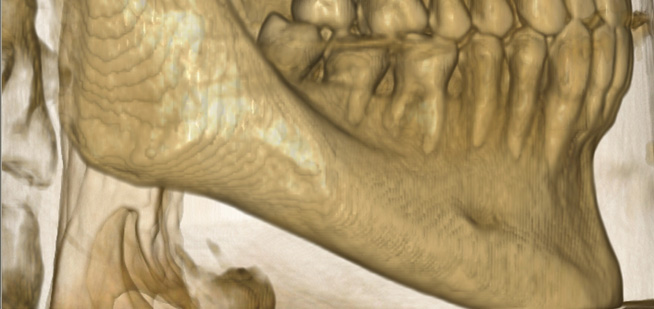

Endo-Perio

Der Facharzt für Endodontie und Periodontologie benötigt Bilder von absoluter Spitzenqualität und Detailschärfe, um Verfahren wie die Behandlung von Zahnbrüchen, die Heilung von Zahngewebe und die Therapie des Kieferkanals vorzunehmen, da er über genaue Details der behandelten Zone und des Krankheitsbilds verfügen muss, um eine wirkungsvolle Behandlung planen zu können. Nur eine eingehende Untersuchung der betroffenen Areale kann Aufschluss über einen mehr oder weniger invasiven Eingriff geben.